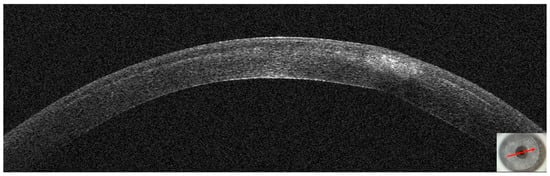

3.1. Patient #1